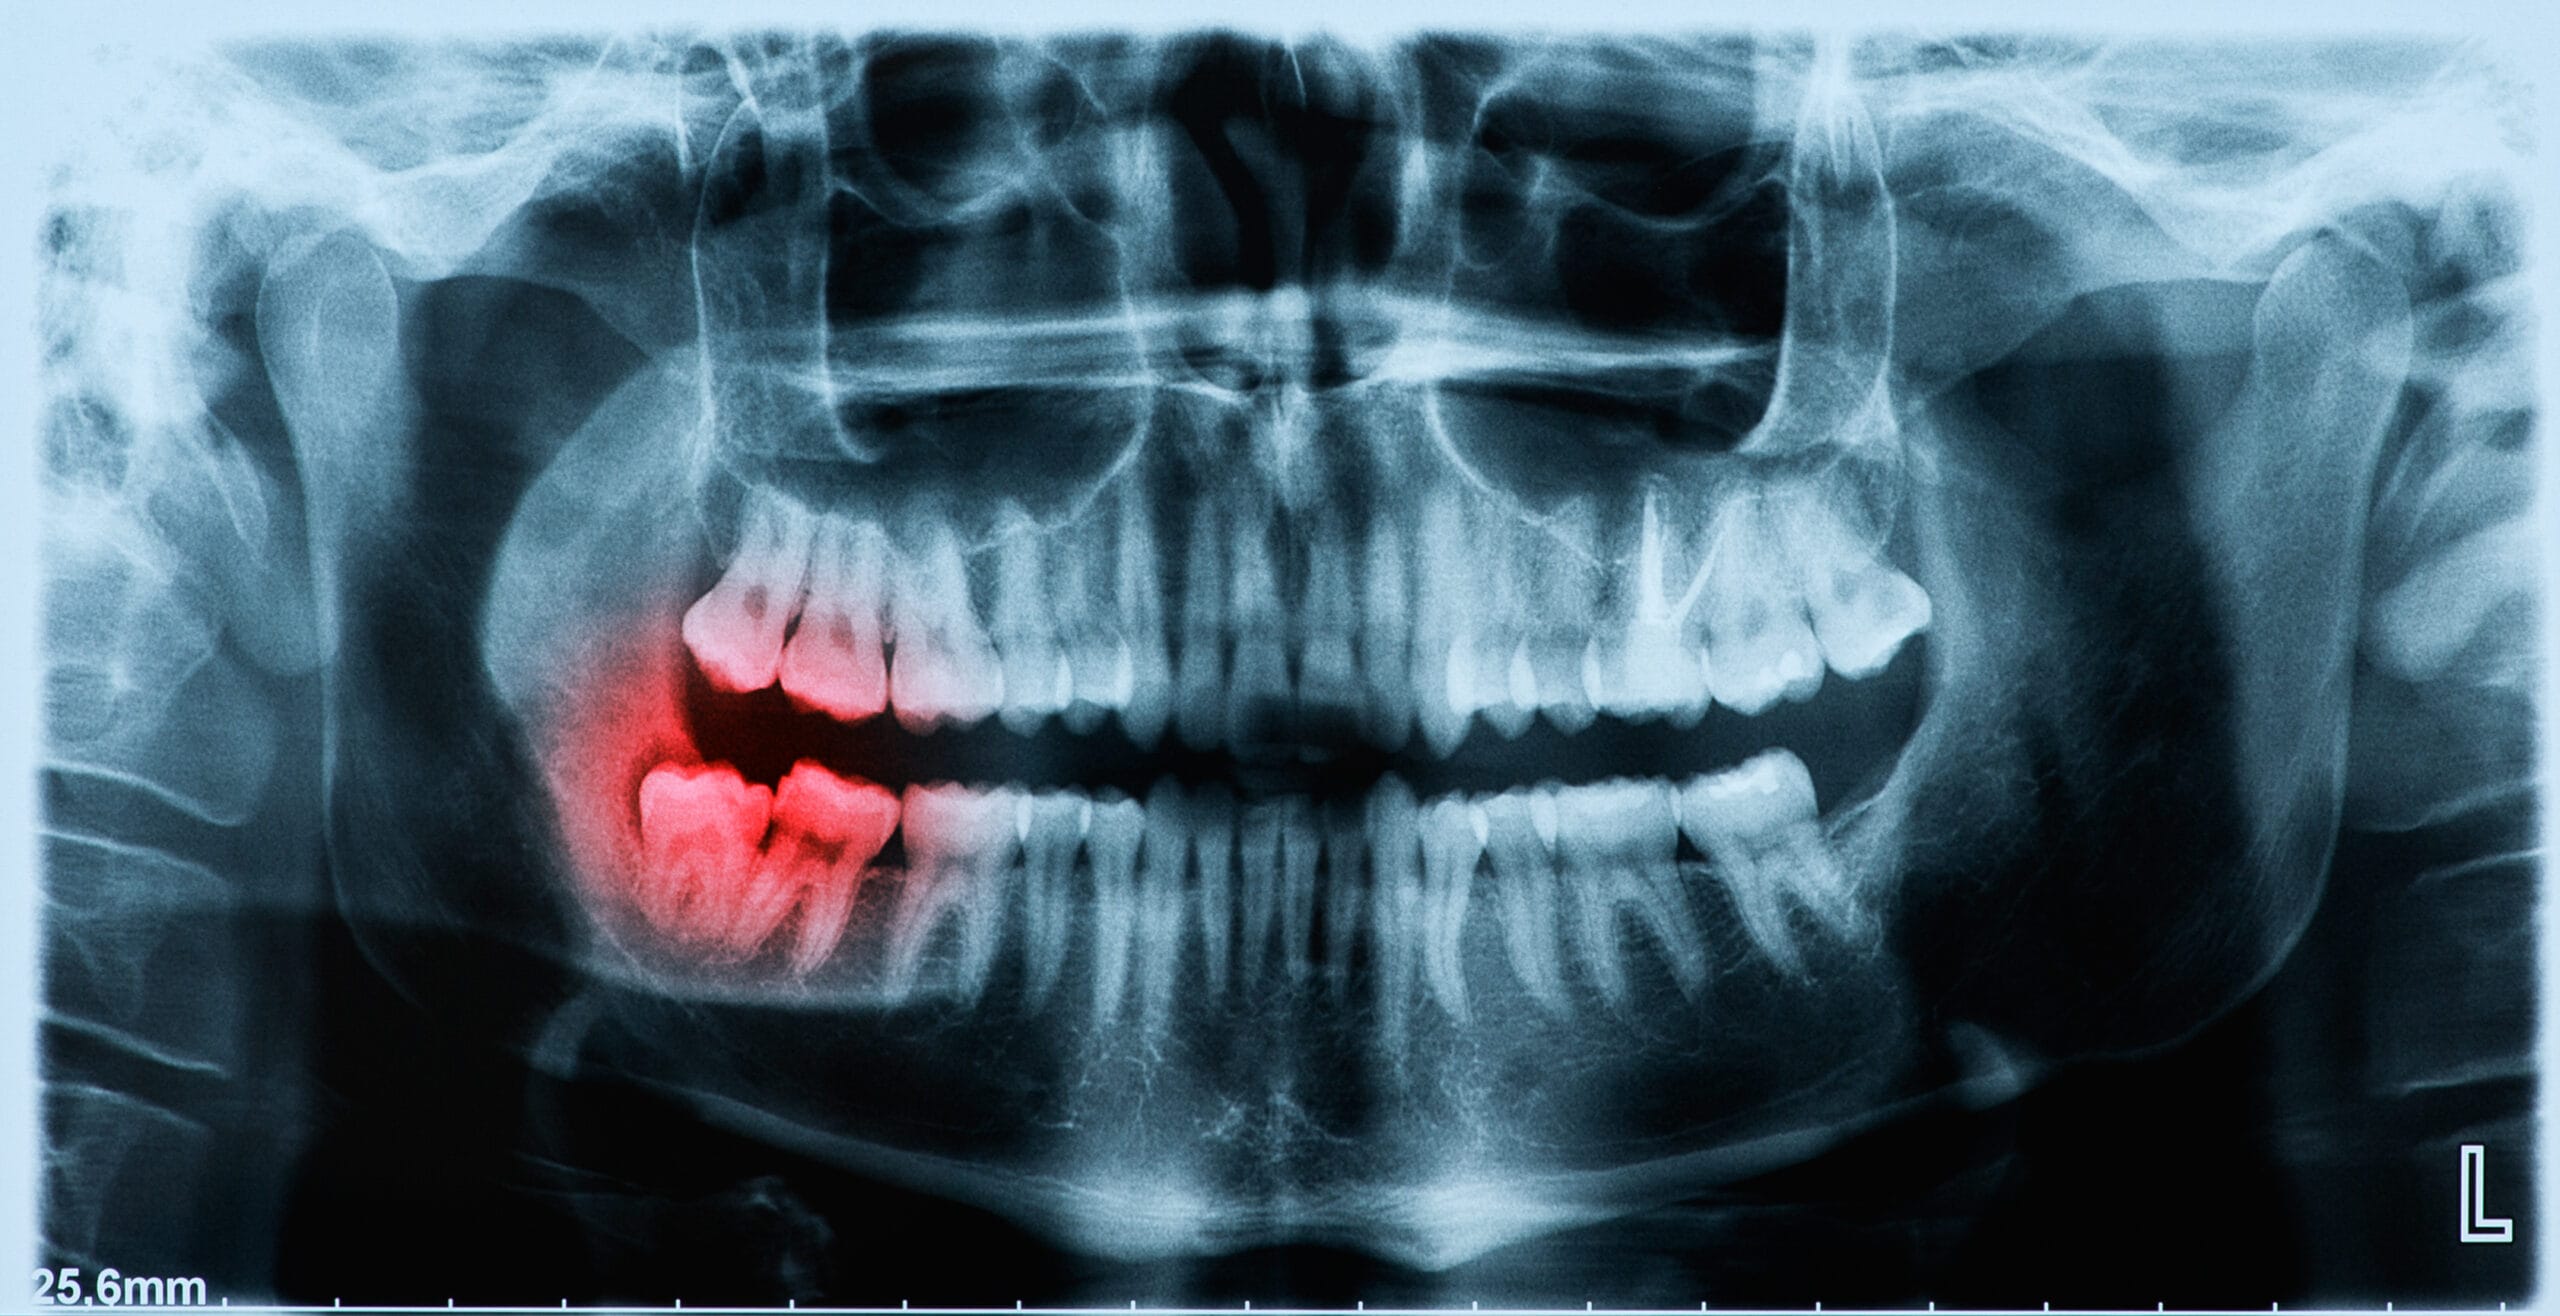

If your tooth is damaged or decayed, and is beyond repair your dentist may decide that the tooth should be extracted. Your dentist will talk you through your options beforehand, to ensure this is the only option for your case as teeth extractions are always a last option.

There are a number of different reasons that a tooth should be removed, for example, if you have the following:

Our clinicians will usually extract your teeth by themselves. However, sometimes the tooth extraction can be slightly more complicated than what they initially thought; therefore you may be referred to a Specialist Oral Surgeon either in a hospital setting or here at the practice.

At Toothcare Dental, we carry out simple tooth extractions, surgical tooth removal and wisdom tooth extractions. In some cases these are classed as minor oral surgery, but our focus is always on removing the tooth as gently and comfortably as possible.